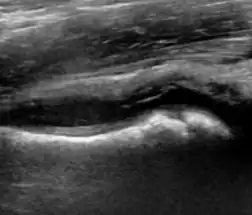

During childhood, ultrasound is a quick method to assess hip pain and quite often may be used to avoid use of irradiating techniques, such as radiography or CT. Ultrasound allows evaluation of joint effusion, synovial thickening and neovascularity, the bone/cartilage contour, and the femoral head-neck alignment. Although sonography is extremely sensitive in detecting increased synovial fluid, it is nonspecific and cannot be used with accuracy to determine the type of fluid. Transient synovitis of the hip, despite being the most frequent cause of pain in children between 3 and 10 years, remains a diagnosis of exclusion. It usually shows anechoic fluid, but echogenic fluid can also be found. The effusion is considered pathologic when it is measured at >2 mm in thickness. The differential diagnosis is wide, including osteomyelitis, septic arthritis, primary or metastatic lesions, LCPD, and SCFE. Discrimination from septic arthritis is challenging, often requiring joint aspiration. In septic arthritis, US is able to demonstrate a hip joint effusion, synovial thickening, and cartilage damage, although the appearances are nonspecific.[1]

A step between the head and the physis can be detected in children with SCFE, while abnormalities in the femoral head contour may suggest the presence of LCPD. In both cases, radiographs are mandatory to confirm diagnosis and severity (Figure 12).[1]

Figure 12:

Normal ultrasound appearance of the femoral head-neck junction. -

Joint effusion in transient synovitis of the hip. -

Flattening of the femoral head in a patient with Perthes disease. -

Step in the femoral head-neck junction in a patient with SCFE.